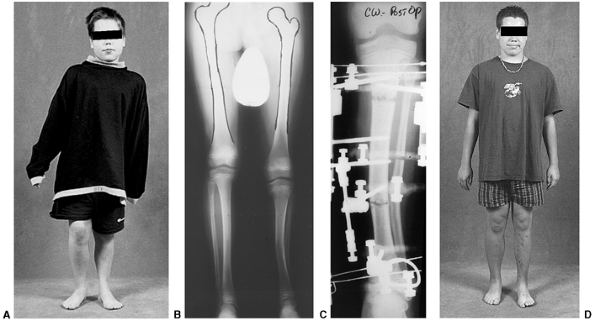

![]() |

|

Figure 28.20 A: Adolescent Blount disease frequently occurs in very large teenagers. The deformity is often bilateral. B:

Long cassette films are used to assess mechanical alignment as well as the anatomic axes of the femur and tibia. Distal femoral deformity is often present as well as proximal tibial varus. C: Procurvatum of the proximal tibia develops, with increased posterior slope of the proximal tibia. D: Distal tibial valgus develops to allow the foot to have flat contact with the floor. E: Restoration of normal alignment may include multilevel osteotomies. Preoperative templates are useful for planning operative strategies. F: In this example, the plan included immediate correction of distal femoral varus using a blade plate and gradual correction of proximal tibial varus and distal tibial valgus using a circular small wire frame. G: Multiplane correction is facilitated with this technique. Adjustments can also be made to correct the procurvatum that may be present. H: The circular frame provides flexibility. It also allows lengthening as needed in cases of unilateral or asymmetric deformity. I: Radiographs confirm the restoration of alignment. Correction is generally well maintained. J: Clinical photo after bilateral treatment shows satisfactory clinical correction compared to the preoperative photo. K: Correction of procurvatum restores normal orientation of the knee. |